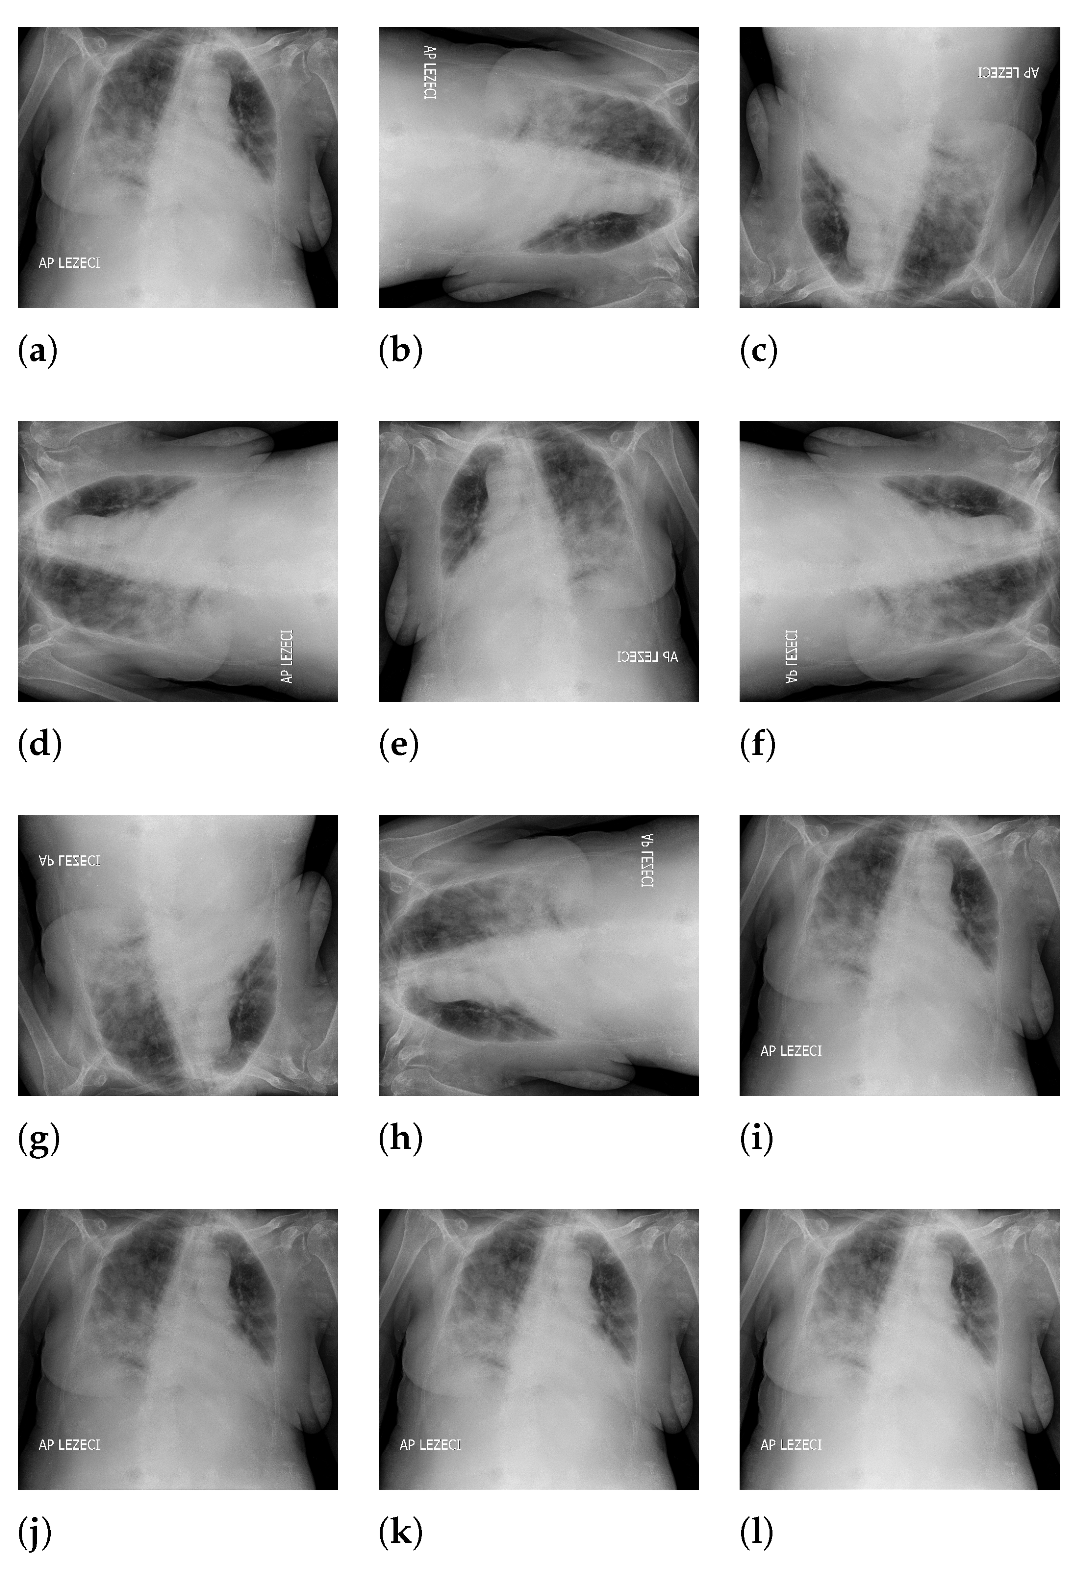

The 90-degree rotation presents an operation that rotates the original image (presented with Figure 3a) by 90 degrees in a clockwise direction around the sagittal axis, as presented in Figure 3b. Following the presented logic, rotations for 180 and 270 degrees were performed as well, as presented in Figure 3c,d. Images rotated by 90 and 270 degrees were resealed in order to have the same dimensions as the original image. Image generation by 180-degree rotation around the longitudinal axis was performed in such a way that the new image represented a mirrored projection of the original image, as presented in Figure 3e. The mirrored image was rotated around the sagittal axis, forming three new variations, as presented in Figure 3f–h. As the final approach to image augmentation, a process of multiplication of all image pixels with a certain factor is proposed. In this case, four different factors (0.8, 0.8, 1.1, and 1.2) were used. The described transformations have been presented on an original image with Figure 3i–l. It is important to notice that such transformations were applied on an augmented set that was created by using all described geometrical transformations. By using such an approach, the new augmented dataset was four times larger than the dataset created by using just geometrical transformations.

Figure 3.

Overview of image augmentation procedure ((a): original image; (b): image rotated for 90 degrees around sagittal axis; (c): image rotated for 180 degrees around sagittal axis; (d): image rotated for 270 degrees around sagittal axis; (e): image rotated for 180 degree around longitudal axis; (f): image rotated for 180 degree around longitudal axis and rotated for 180 degree around sagittal axis; (g): image rotated for 180 degree around longitudal axis and rotated for 180 degree around sagittal axis; (h): image rotated for 180 degree around longitudal axis and rotated for 270 degree around sagittal axis; (i): image with pixels multiplied by a factor 0.8; (j): image with pixels multiplied by a factor 0.9; (k): image with pixels multiplied by a factor 1.1; (l): image with pixels multiplied by a factor 1.2).